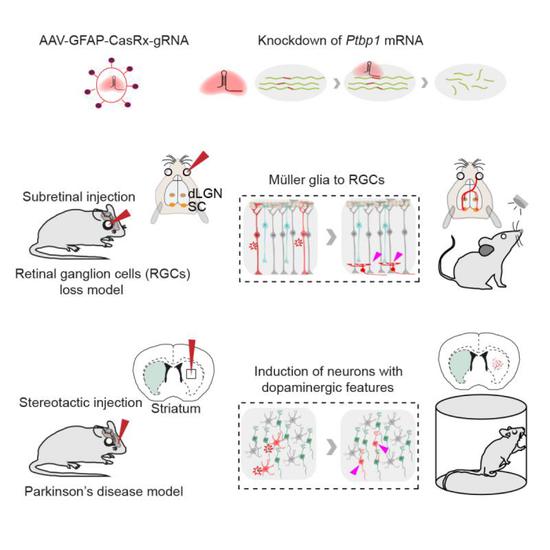

帕金森病,从神经科学的角度来说,是因为神经元死亡而产生的疾病,但人类神经细胞不可再生。科学家大胆猜想,是不是可以让别的细胞“转职再就业”,变成神经元细胞。如今,上海科学家的最新研究成果正将此变为现实。昨天深夜,《细胞》期刊在线发表了题为《通过CRISPR-CasRx介导的胶质细胞向神经元的转分化治疗神经性疾病》的研究论文。该研究由中科院脑科学与智能技术卓越创新中心(神经科学研究所)、神经科学国家重点实验室杨辉研究员以及博士后周海波领导完成。

在常见的神经性疾病中,视神经节细胞死亡导致的永久性失明和多巴胺神经元死亡导致的帕金森病是尤为特殊的两类,它们都是由于特殊类型的神经元死亡导致。随着医学技术的进步,人们发现只要适当调控某些基因,就能让细胞出现所谓的转分化现象,也就是从一种细胞变成另一种细胞。而在人类大脑中,胶质细胞的数量是神经细胞的十倍以上,而且还能不断地产生。如果将人脑中的胶质细胞变成多巴胺神经元,正好可以顶替帕金森病患者脑中死去的神经元。